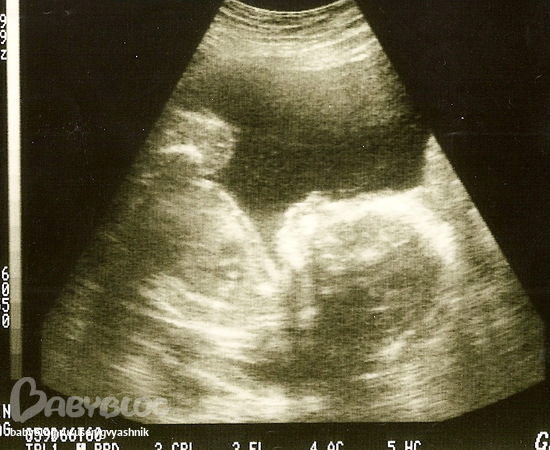

12 недель скриннинг

20 недель

Муж говорит, что профиль очень "мужской")))